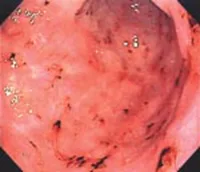

La gastritis crónica por Hpylori se caracteriza por:

Gastritis crónica

La gastritis crónica autoinmune se caracteriza por: